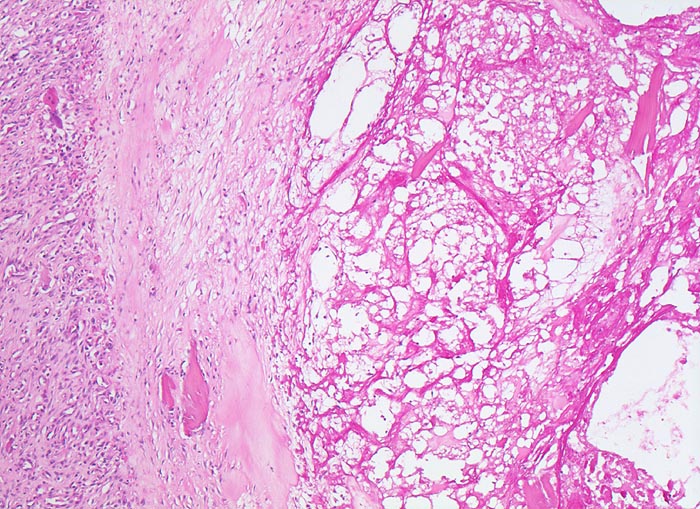

Der progrediente Knorpelverlust führt zum Freiliegen der knöchernen Deckplatte. Der subchondrale Knochen antwortet mit einer elfenbeinartigen Sklerose in Arealen vermehrter Belastung (=Eburnisation). Der traumatisierte subchondrale Knochen kann als Folge einer Knochennekrose pseudozystisch degenerieren (Geröllzystenbildung). Am Rand des Knochens, ausserhalb der Belastungszonen bilden sich irreguläre Knochenneubildungen (Randosteophytenbildung ev. mit Verdoppelung des Gelenkknorpels). Fragmentierungen dieser Osteophyten oder des Gelenkknorpels führen zu intraartikulären freien Körpern (=Gelenkmäuse) und einer Detritussynovialitis (> 1146) (> 1038) (> 539).

• Deformierte Gelenkfläche.

• Weitgehendes Fehlen des hyalinen Gelenkknorpels.

• Sekundäre Sklerose der freiliegenden Spongiosa mit Anbau von breiten Faser- und Lamellenknochensäumen an die alten Bälkchen.

• Herde von metaplastischem Faserknorpel in der Gelenkfläche.

• Nekrosebezirk in der Spongiosa (Geröllzyste) umgeben von einem Granulationsgewebssaum und Narbengewebe.